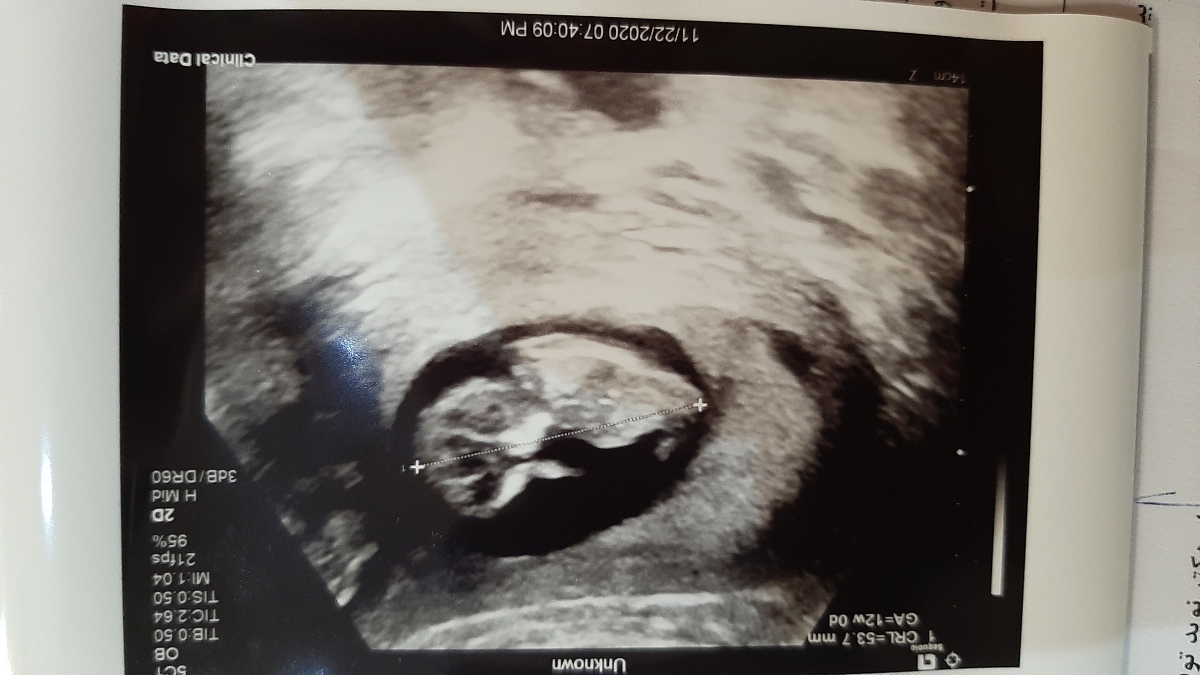

من ۱۲هفته و ۴ روز بود رفتم ان تی

هر وقت دوازده هفته و چهار روزت شد برو

من دکترم گفت بهترین زمان اومدی